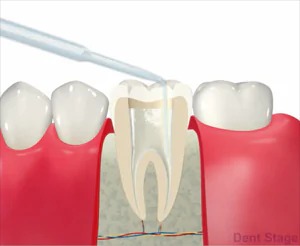

5根管洗浄

内部の消毒を行います。一般的には次亜塩素酸水溶液を用います。当院では、より洗浄効果の高い次亜塩素酸水溶液とEDTA(根管内に詰まった切削片を溶かす)を交互に使い洗浄します。

6根管貼薬

根管内に水酸化カルシウム製剤を置きます。

さらに、根管内の細菌の現症を行って、症状が落ち着くのを待ちます。